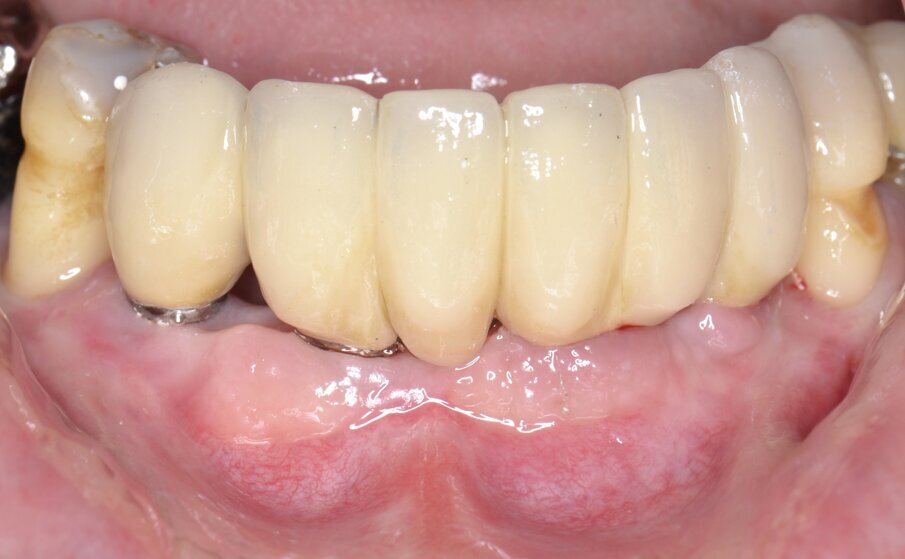

Al momento della riapertura, l’immagine intraoperatoria rivela una sostanziale risoluzione dei difetti peri-implantari con abbondante rigenerazione di tessuto neoformato che, in alcuni siti, arriva a coprire la testa dell’impianto endosseo (Fig. 13). Dopo aver condizionato in modo appropriato i tessuti molli mediante viti di guarigione (Fig. 13) una protesi definitiva di tipo fisso in metallo-ceramica viene cementata sugli abutments implantari (Fig. 14). Il controllo radiografico eseguito in occasione del follow-up a 12 mesi rivela un mantenimento ottimale dei volumi ossei rigenerati e un’evidente corticalizzazione del tessuto osseo peri-implantare (Fig. 15).

Fig. 15 - Protesi definitiva in metallo-ceramica.